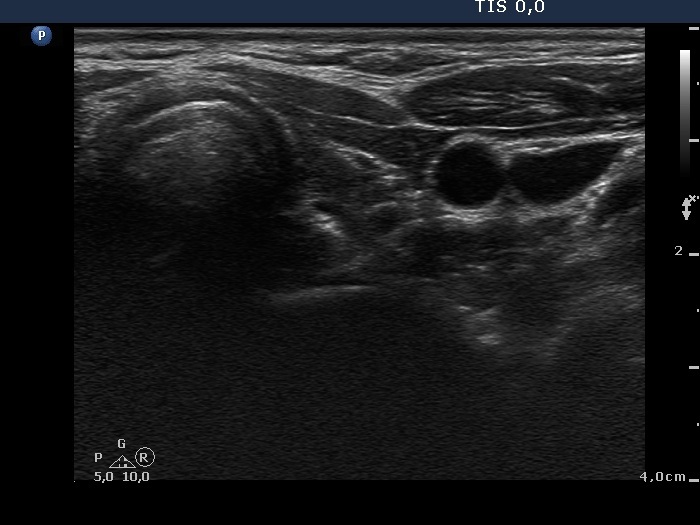

Six months after initial investigation (second row):

Clinical presentation: she had no complaints till the last several week, then she noticed increase in heart rate and fatigue.

Palpation: both thyroids were enlarged.

Functional state: hyperthyroidism with TSH-level 0.09 mIU/L, FT4 28.2 pM/L, FT3 12.8 pM/L.

Ultrasonography: the thyroids were hypoechogenic and presented increased vascularization.

Clinical diagnosis: recurrent hyperthyroidism caused by Graves's disease. We administered daily 20 mg methimazole. 2 months later when FT4 level has normalized the patient underwent radioiodine therapy.